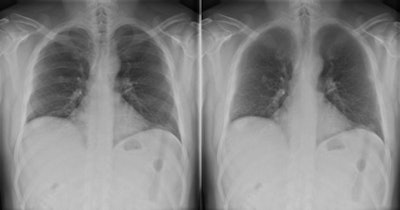

Bone suppression computer-aided detection (CAD) software can provide a significant boost for diagnosis of pulmonary nodules, especially those of moderate and subtle conspicuity, Dutch researchers have reported.

In a study conducted at Radboud University Nijmegen Medical Center, posteroanterior (PA) and lateral digital chest radiographs of 111 patients (average age 65) with a CT-proven solitary nodule (median diameter 15 mm), and 189 controls (average age 63) were read by five radiologists and three trainees. The total number of missed lesions for the eight readers went down from 255 with chest x-rays (CXR) only to 189 with CXR and bone-suppressed images (BSI).

"Obscuration of lung cancer by overlying bone structures represents a major contributor to misdiagnosis," they pointed out. "A new software product has been developed to suppress ribs and clavicles in the original image without requiring special hardware or increase of patient dose caused by double exposures."

Bone suppressed images were generated by ClearRead Bone Suppression 2.4 (Riverain Technologies). This software uses advanced image processing to construct a bone suppressed PA chest image, and it can produce an image that has the same characteristics as the original image with respect to gradation, detail contrast, and size. It has U.S. Food and Drug Administration (FDA) approval.

Receiver operating characteristic (ROC) analysis showed improved detection with use of BSI compared with CXR alone (AUC = 0.883 versus 0.855; p = 0.004). Performance also increased at high specificities exceeding 80% (pAUC = 0.136 versus 0.124; p = 0.0007). Operating at a specificity of 90%, sensitivity increased with BSI from 66% to 71% (p = 0.0004). Increase of detection performance was highest for nodules with moderate and subtle conspicuity (p = 0.02; p = 0.03).